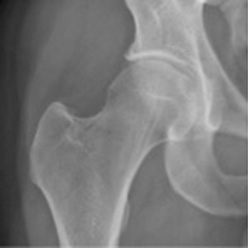

Röntgenbild Arthrose am Hüftgelenk (Coxarthrose)